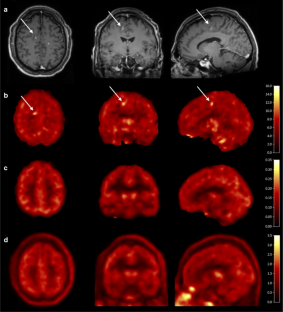

Mean test V T values (ml cm−3) were 3.9 ± 1.4 in the whole brain gray matter (GM), 3.6 ± 1.2 in the whole brain white matter (WM) or normal-appearing white matter (NAWM), and 3.3 ± 0.6 in MS WM lesions; mean retest V T values were 3.7 ± 1.0 in GM, 3.3 ± 0.9 in WM/NAWM, and 3.3 ± 0.7 in MS lesions. Test-retest results showed a mean absolute TRV ranging from 7 to 9 % across GM, WM/NAWM, and MS lesions. High-affinity binders demonstrated 30 % higher V T than medium-affinity binders in GM. Focal 11C-PBR28 uptake was detected in two enhancing lesions of the active MS patient.